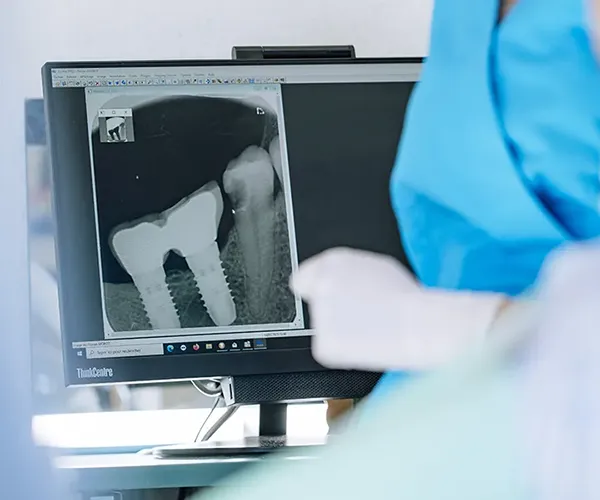

Inconvénient mineur : sauf dans certains cabinets équipés en CFAO (Conception et Fabrication Assistées par Ordinateur), cette technique nécessite 2 séances de soins, car une étape de laboratoire s’intercale entre la réalisation de la cavité et la pose et le scellement des inlays onlays réalisés en métal, en résine composite ou en céramique.